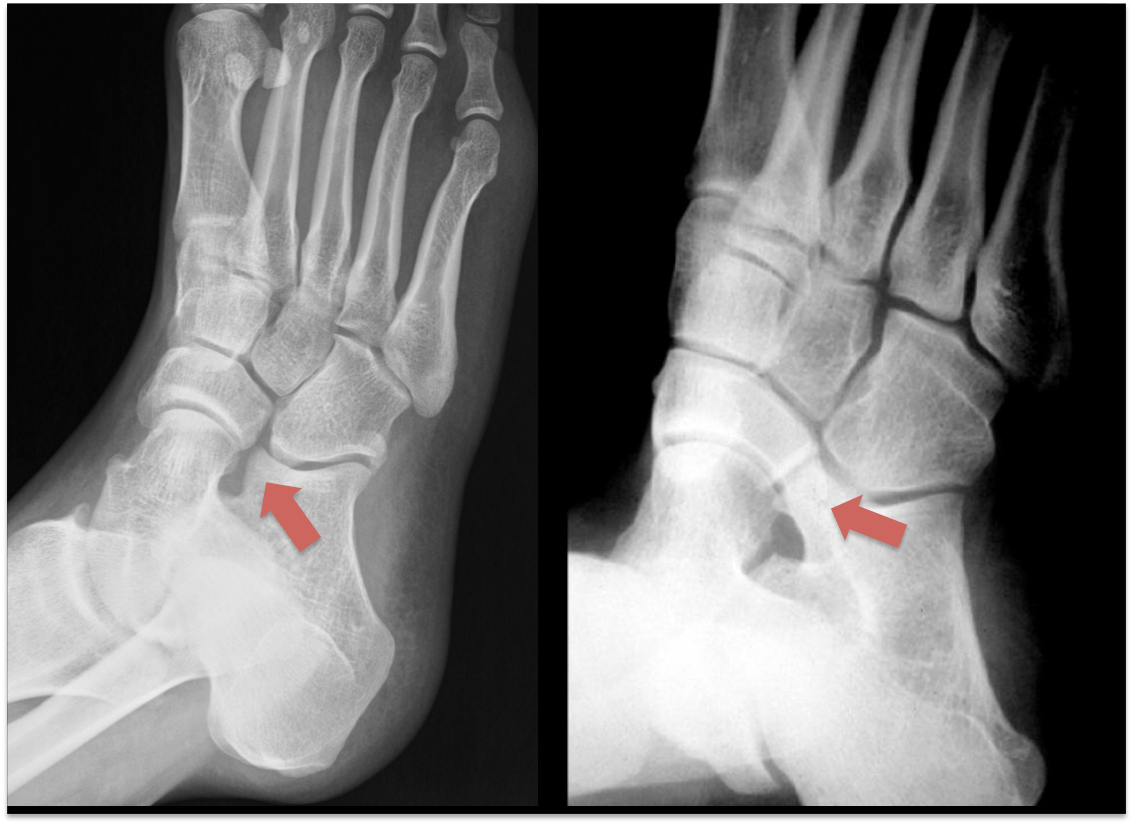

Radiografias (Raio-X):

São os exames iniciais. Podem mostrar a coalizão, especialmente as ósseas, em projeções específicas.